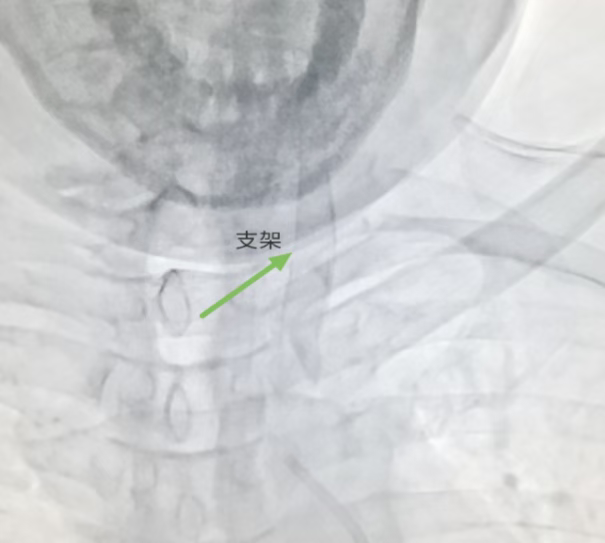

术前DSA示:左侧锁骨下动脉重度狭窄,左侧颈动脉内大量血栓形成,管腔狭窄。

术后DSA:支架置入在位,狭窄血管恢复正常血流。

术前OCT:颈动脉内大量血栓,伴有部分破溃,并伴有局部管腔狭窄

术后OCT:左侧颈动脉血管管腔狭窄明显改善,支架管壁伴有局部血栓,少量组织脱垂。